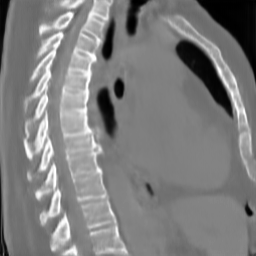

The results presented in Table 1 and 2 show our proposed method’s performance on unconditional 3D brain MR and chest CT image generation. Our proposed approach not only outperforms most comparing methods in FID and MS-SSIM metrics, it also has the lowest inference GPU memory footprint at a resolution of and was the only diffusion-based method that could be trained at a resolution of . Operating in the wavelet domain and profiting from the reduced spatial dimension also results in a relatively short inference time of / at the respective resolutions. Compared to the results presented in [23], we did not find that incorporating wavelet information into the network’s feature space (WavU-Net) increased the model’s performance. Qualitative results of our proposed method (WDM) are shown in Fig. 2 and 3. A qualitative comparison of samples produced by all evaluated methods can be found in the Supplementary Material.